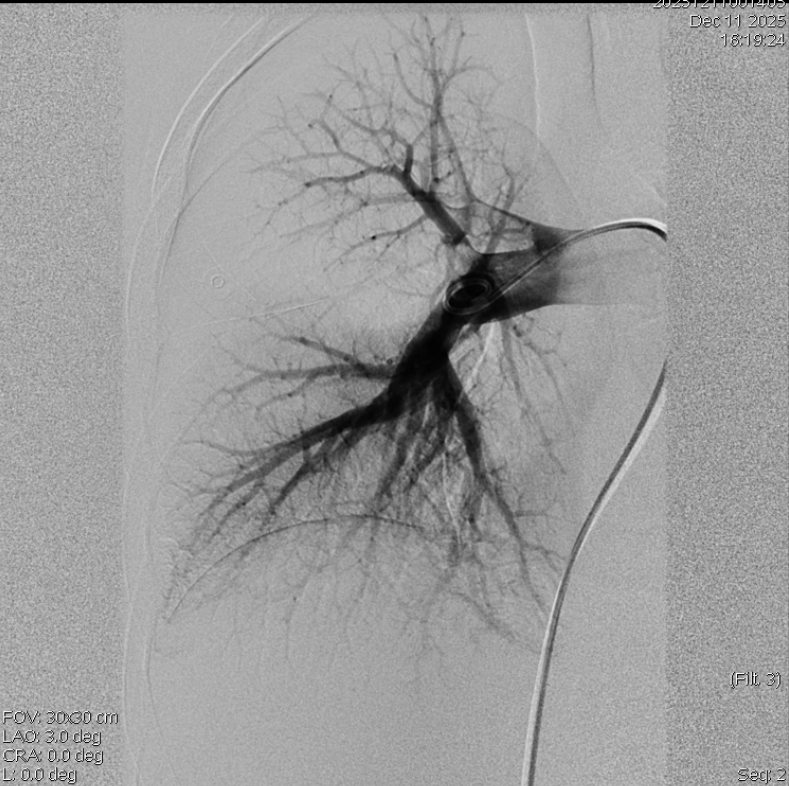

左、右肺动脉造影

术中导管抽吸血栓、支架取栓